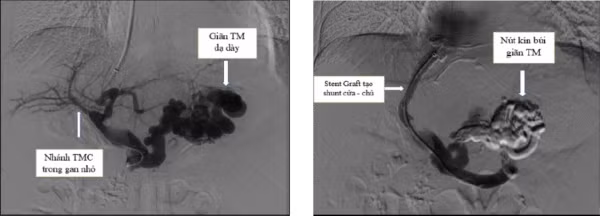

Hình ảnh xơ gan và dịch ổ bụng mức độ nhiều trên phim chụp cắt lớp vi tính của người bệnh - Ảnh BVCC

Tuy nhiên, do tình trạng giãn tĩnh mạch thực quản nhiều và kích thước lớn nên người bệnh được đánh giá có nguy cơ chảy máu tái phát rất cao. Cùng với đó, người bệnh có tình trạng chướng bụng nhiều do dịch tự do trong ổ bụng.

Sau khi được điều trị tích cực ban đầu, người bệnh được các bác sĩ chuyên khoa Điện quang can thiệp hội chẩn và thăm khám, xác định tình trạng bệnh có thể diễn biến tái phát chảy máu bất cứ lúc nào và có thể đe dọa tính mạng.